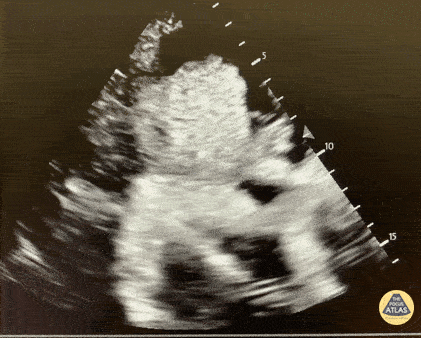

This clip portrays a pericardial effusion with tamponade physiology found in a patient suffering from myxedema coma after she lost access to her levothyroxine. Jacob Long, Medical Student Alicia Hoban, MD Michael Gomez, DO